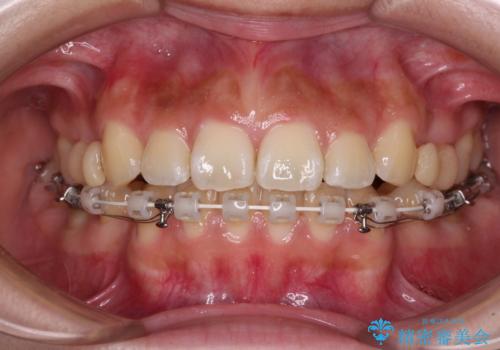

- ハーフリンガル

- 口元から飛び出てしまう前歯を気にして来院された患者様です。

上下前歯が嘴のように前方に突出しており、唇が閉じにくい状態であったため、上下左右の第一小臼歯4本を抜歯して、口元の突出感を改善することとしました。

目立たない装置を希望とのことで、上顎が裏側、下顎が表側のハーフリンガル装置を用いることとしました。